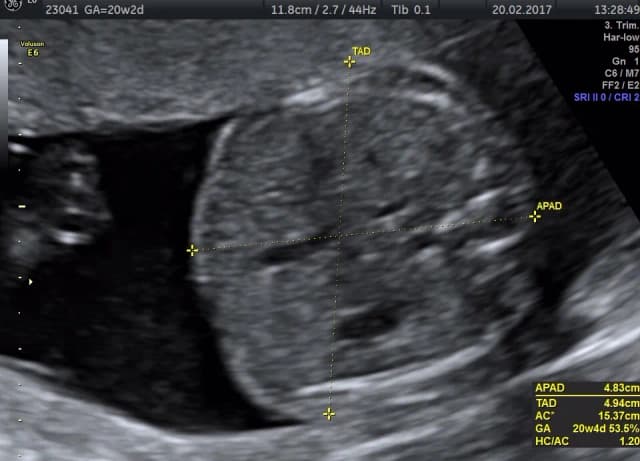

Tag jakie są etapy badania połówkowego